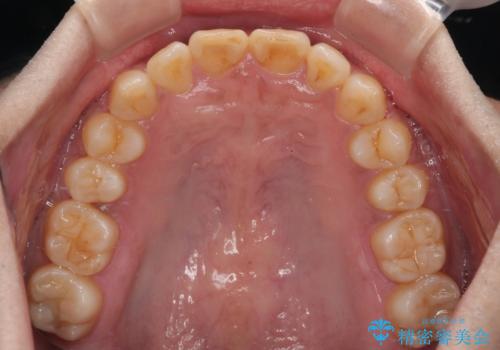

上顎歯列を遠心移動させたことで、前歯の叢生が解消されても前歯が前突することなく、左右ともに理想的な咬み合わせを達成することができました。